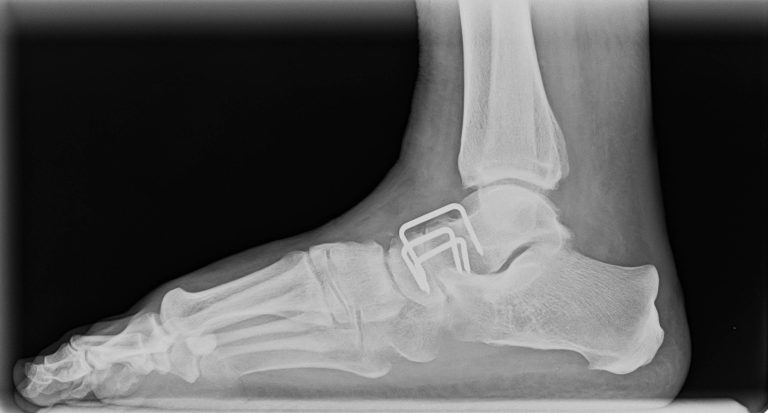

Što je CT

Kompjuterizirana tomografija se služi x-zrakama kao i rendgen za dijagnostiku, čak ima i jače zračenje od rtg-aparata, ali daje i jasniju i detaljniju sliku snimanog organa ili područja u tijelu boles